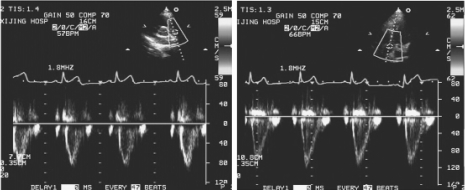

2.频谱特点 正常心脏各部位频谱特点及时相不同,见表10-7。正常房室瓣(图10-32)及半月瓣血流频谱见图10-33。

图10-33 左图:肺动脉瓣上正常血流频谱图;右图:主动脉瓣上正常血流频谱图